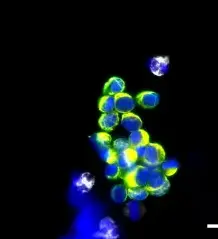

Example images from patient blood samples

Cluster of EMT CTCs - breast

Examples of Portrait+ CTC staining kit samples